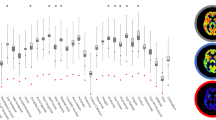

Distribution of synaptic density and Aβ deposition in normal cognition, aMCI, and dementia

Analyses of both [11C]UCB-J and [11C] PiB DVR demonstrated significant effects of group ([11C]UCB-J: F (2,54) = 10.1, P = 0.0002, [11C]PiB: F (2,54) = 56.9, P < 0.0001), ROI ([11C]UCB-J: F (11,594) = 318.9, P < 0.0001, [11C]PiB: F (11,594) = 257.4, P < 0.0001), and group × ROI interaction ([11C]UCB-J: F (22,594) = 2.3, P = 0.001, [11C]PiB: F (22,594) = 43.3, P = < 0.0001) as predictors of SV2A and Aβ binding. Consistent with our recent publication [18], one-way ANOVA with post hoc, false discovery rate (FDR)-corrected unpaired t-tests revealed significant reductions of SV2A binding in both aMCI and dementia participants (compared to CN) across the majority of neocortical regions, with the exception of the anterior cingulate and medial occipital cortices (Fig. 1a, c, Supplementary Table 1). Group differences were largest in the hippocampus, entorhinal cortex, and lateral temporal cortex. The prefrontal, PCC/precuneus, and lateral occipital cortices also demonstrated significant reductions in SV2A binding in the dementia group, while non-significant trends of SV2A reduction were observed in aMCI participants (as compared to the CN group). One-way ANOVA with post hoc, FDR-corrected unpaired t-tests of [11C] PiB revealed significant and broadly distributed Aβ deposition across all neocortical regions in both aMCI and dementia (compared to CN) participants, with the exception of the hippocampus (Fig. 1b, d, Supplementary Table 2). No differences were observed in either SV2A or Aβ binding between aMCI and dementia groups across all analyzed ROIs. Average group images of DVR demonstrated visible reduction and deposition of SV2A and Aβ binding, respectively, in both aMCI and dementia groups (Fig. 1a, b), compared to the CN group.

Comparison of SV2A and Aβ deposition in CN, aMCI, and dementia groups. Coronal sections of average parametric images of DVR for a [11C]UCB-J and b [11C] PiB in CN, aMCI, and dementia groups. Averaged images were created after co-registration to a common MNI template and overlaid on an MNI template T1 MRI. Parametric images adhere to radiological convention, with orientation denoted in the first coronal section of each image series. Quantification of between-group differences in c [11C]UCB-J DVR and d [11C] PiB DVR across all ROIs. One-way ANOVAs within each ROI with post hoc unpaired t-tests, FDR-corrected for multiple comparisons (3 comparisons for diagnostic groups), demonstrated significantly lower [11C]UCB-J DVR and significantly higher [11C] PiB DVR in both the aMCI and dementia participants (as compared to CN) across most analyzed regions. No group differences were observed in either SV2A or Aβ binding between aMCI and dementia participants across all analyzed ROIs. # denotes significant post hoc group differences between aMCI and CN. # P < 0.05, ## P < 0.001, ### P < 0.0001. * denotes significant group post hoc differences between dementia and CN. * P < 0.05, ** P < 0.001, *** P < 0.0001. Abbreviations: DVR, distribution volume ratio using a whole cerebellum reference region; PCC, posterior cingulate cortex, aMCI: amnestic mild cognitive impairment; CN: cognitively normal; MNI, Montreal Neurological Institute; MRI, magnetic resonance image; PET, positron emission tomography; ROI, region of interest; SV2A, synaptic vesicle glycoprotein 2A; PiB, Pittsburgh Compound B; FDR, false discovery rate

Volumetric MRI was used to investigate gray matter volume differences between CN, MCI, and dementia groups (Supplementary Table 3). Correction for partial volume effects revealed continued significant reductions of SV2A binding in medial temporal regions in both participants with aMCI and dementia, as well as lateral parietotemporal reductions of SV2A binding in the dementia group only. After correction for partial volume effects, Aβ deposition remained significantly elevated across all neocortical regions in both aMCI and dementia participants, with the exception of the hippocampus (Supplementary Figure 2, Supplementary Tables 1 & 2).

Exploratory whole brain analyses were also performed on both a regional and surface-based level. On a regional level, the relationship between global Aβ deposition and SV2A binding in all FreeSurfer regions suggested negative correlations with right-sided subcortical structures in aMCI participants, including the hippocampus, amygdala, caudate, accumbens area, and ventral diencephalon (Fig. 3a). In participants with dementia, however, inverse associations were observed primarily with right-sided cortical regions, including caudal middle frontal, pars triangularis, supramarginal, superior parietal, and inferior parietal regions (Fig. 3b). Surface-based analyses of these same relationships revealed that global Aβ was negatively correlated with SV2A binding in a small cluster of vertices within the right lateral temporal cortex in participants with aMCI (Supplementary Figure 3A). In participants with dementia, by contrast, negative associations with SV2A binding were more widespread across the right frontal, right parietotemporal, and right lateral occipital cortices (Supplementary Figure 3B). No differences remained significant after permutation-based correction for multiple comparisons.

Brain maps of correlations between global Aβ deposition and SV2A in aMCI and dementia. Brain maps were created by producing images with the voxels in each FreeSurfer region set uniformly to the calculated Pearson r for that region and overlaid on an MNI template T1 MRI. Correlations were across all 84 lateralized FreeSurfer brain regions and displayed only for regions with uncorrected P < 0.05 in both the a aMCI and b dementia diagnostic groups. MR image slices adhere to radiological convention, with orientation denoted in the first coronal section of each image series. Abbreviations: DVR, distribution volume ratio using a whole cerebellum reference region; aMCI, amnestic mild cognitive impairment

Analyses investigating the relationship between regional Aβ deposition and synaptic density in all FreeSurfer regions suggested few correlations in aMCI participants (Fig. 4a), while analyses restricted to participants with dementia revealed inverse associations across bilateral prefrontal, temporal, and parietal, and occipital (both medial and lateral) cortical regions (Fig. 4b). These inverse associations were strongest in right-hemisphere regions. In addition, consistent with the previous analysis, positive correlations were observed in the bilateral hippocampi of dementia participants.

Brain maps of correlations between regional Aβ deposition and SV2A in aMCI and dementia. Brain maps were created by producing images with the voxels in each FreeSurfer region set uniformly to the calculated Pearson r for that region and overlaid on an MNI template T1 MRI. Correlations were across all 84 lateralized FreeSurfer brain regions and displayed only for regions with uncorrected P < 0.05 in both the a aMCI and b dementia diagnostic groups. MR image slices adhere to radiological convention, with orientation denoted in the first coronal section of each image series. Abbreviations: DVR, distribution volume ratio using a whole cerebellum reference region; aMCI, amnestic mild cognitive impairment